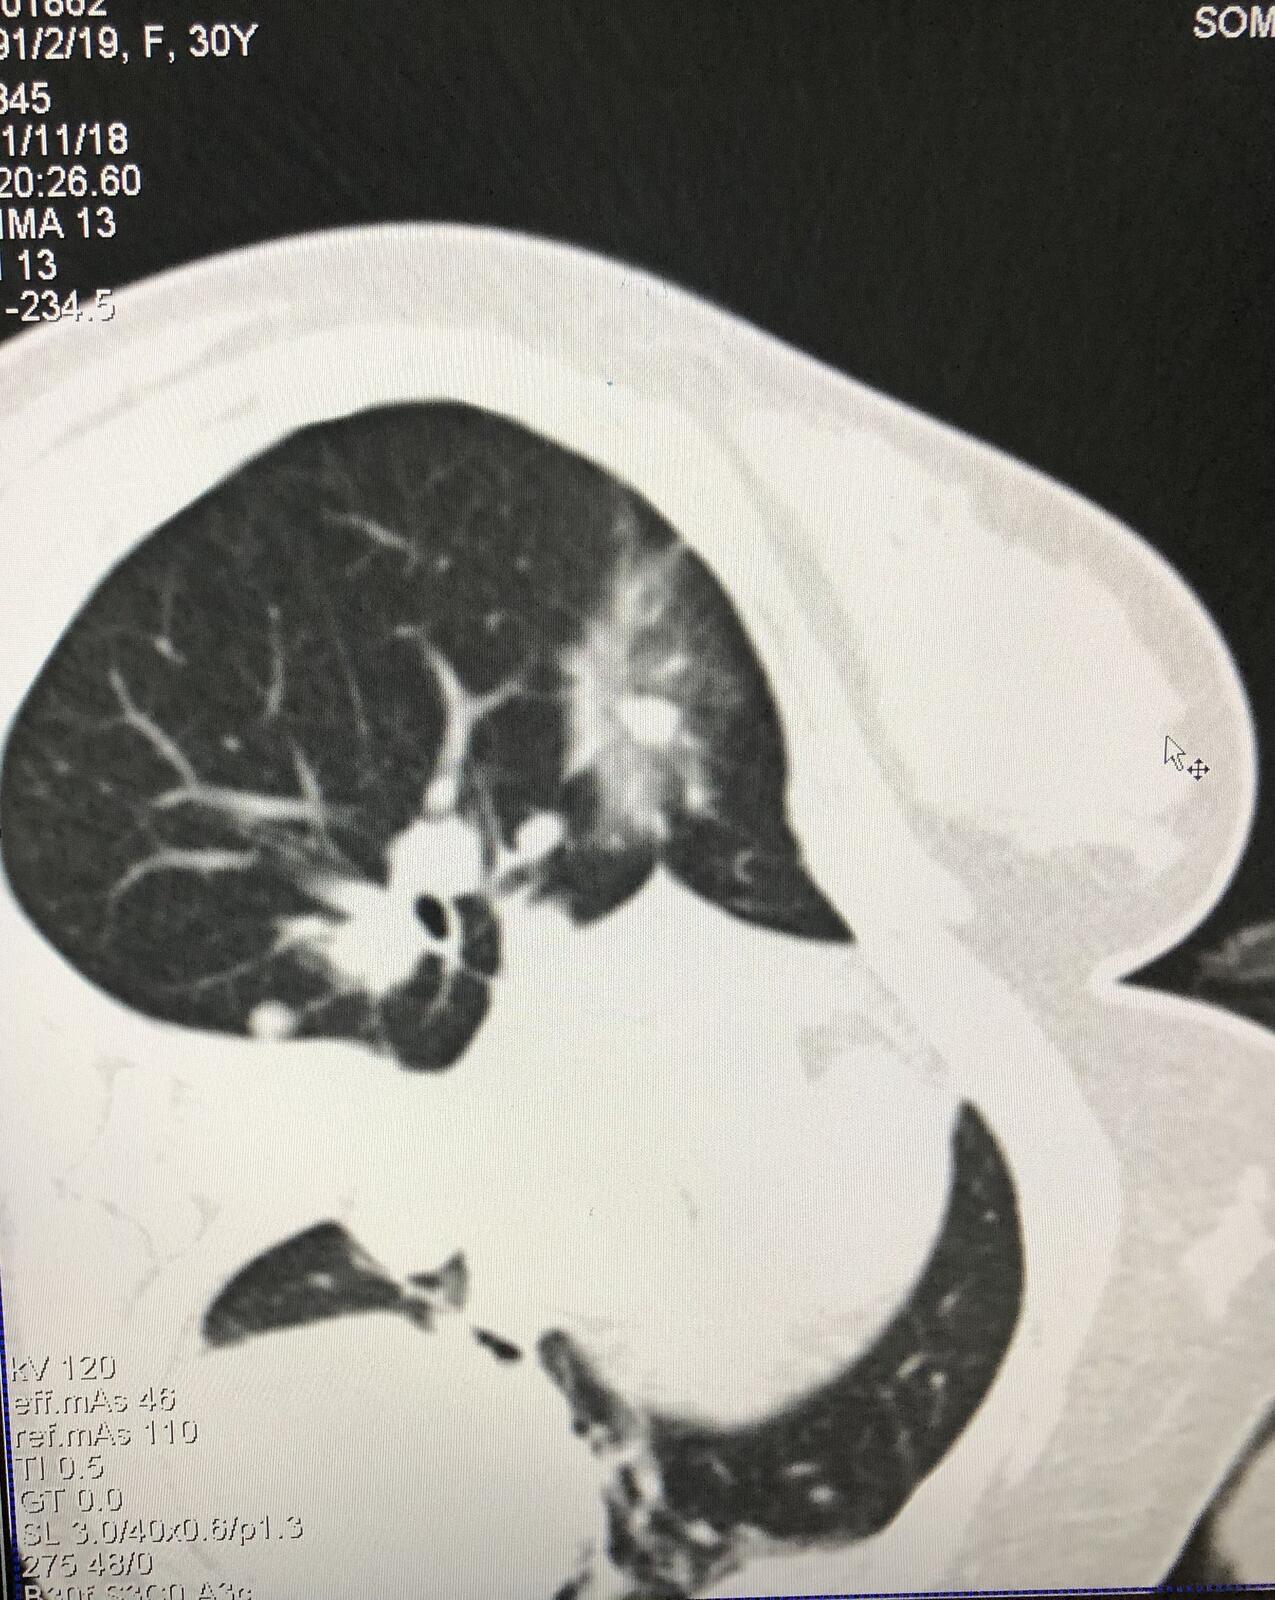

先22g细针穿刺病灶,然后在细针参照下穿刺微波消融针并就行消融治疗。